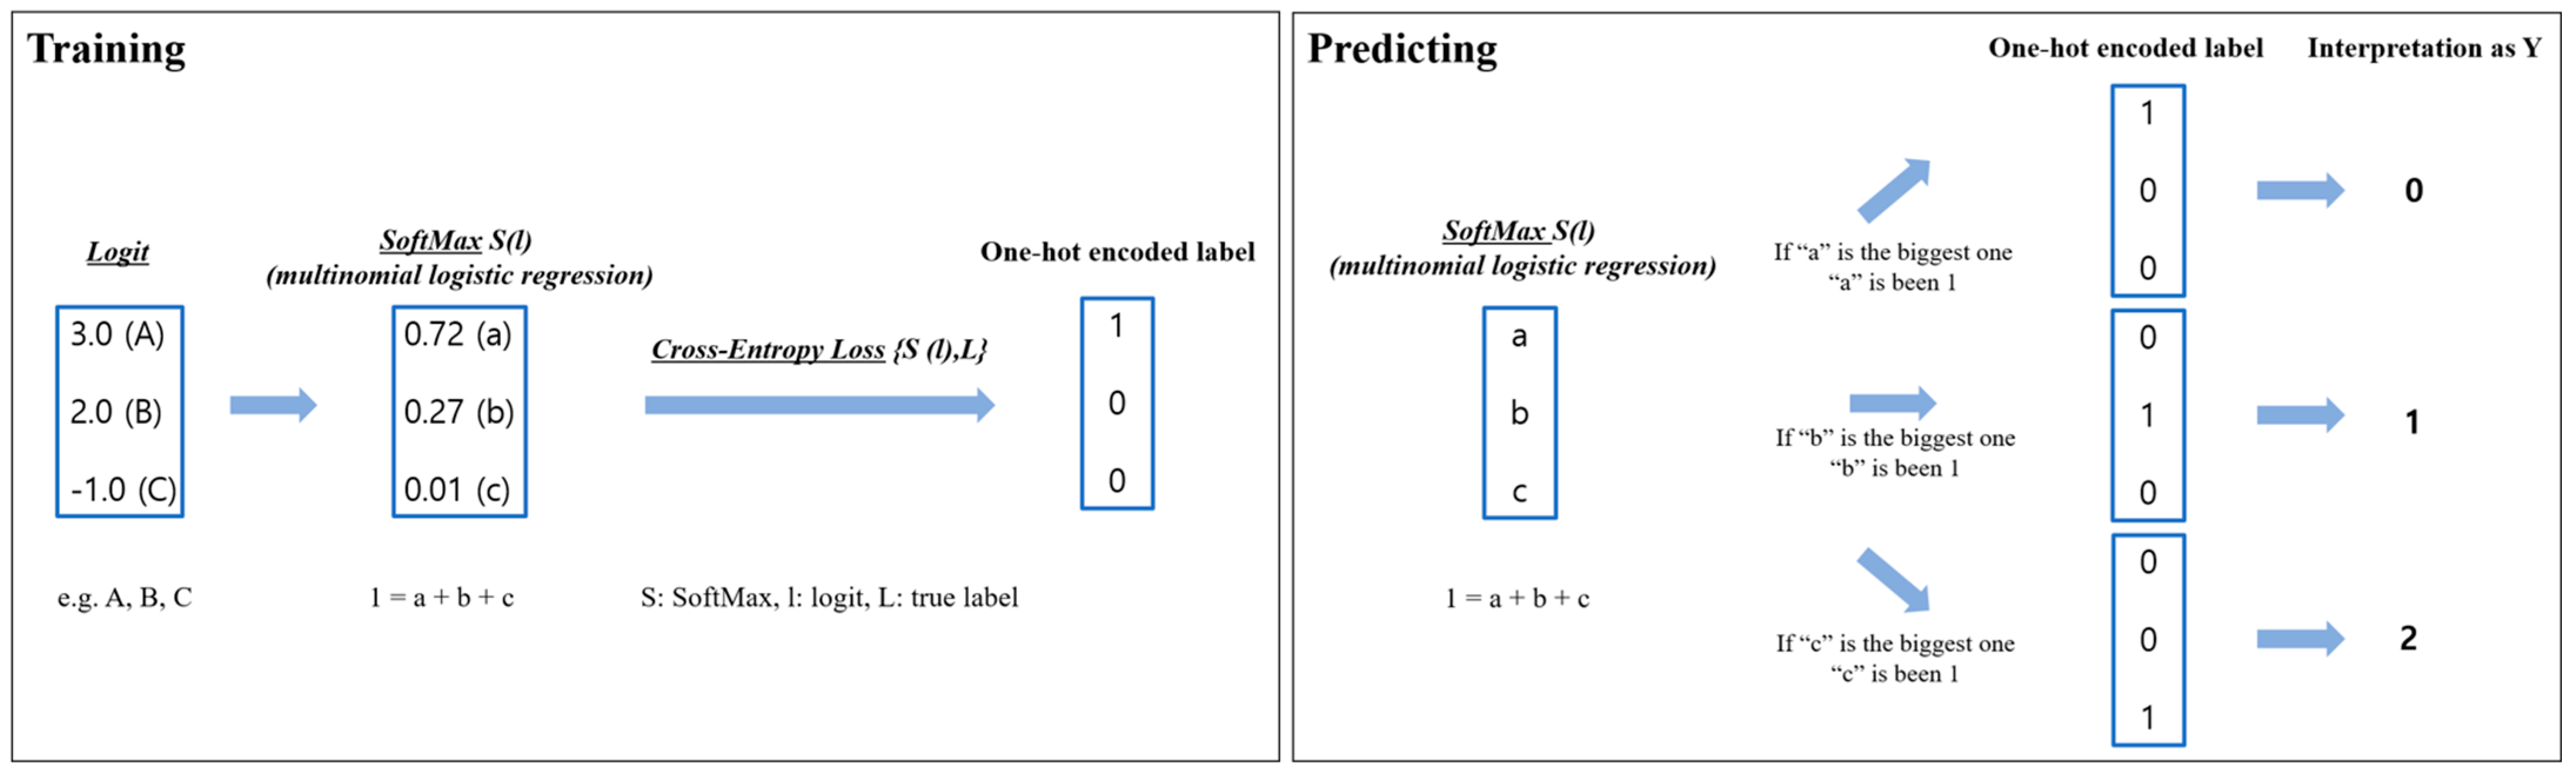

Appendix A. A Detailed Explanation of Algorithms and Models

Appendix A.1. Model Explanation

- ⮚

- Logistic regression

- ⮚

- SoftMax (S)

- ⮚

- Cross-Entropy Loss (CE)